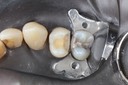

Kyle Chock #14 pre-op